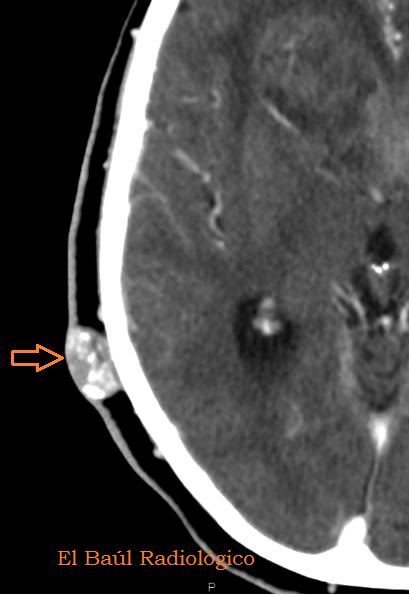

FIGURA 4) Otro quiste sebáceo, totalmente calcificado. Es redondo y está separado de la tabla externa del cráneo, característica que le distingue de un osteoma frontal.

(Anothersebaceous cyst, rounded and fullycalcified.It is separated fromthe outer tableof the skull, a feature that distinguishes itfrom afrontalosteoma)

FIGURA 5) En los quistes sebáceos calcificados, la densidad puede ser muy elevada, tanto como la del hueso compacto, 1168 UH, pero no por eso pueden etiquetarse de osteomas.

(Inhighly calcifiedsebaceous cysts, the density is usually very high, such as compact bone,UH1168, but not for thatshould belabeledosteomas)